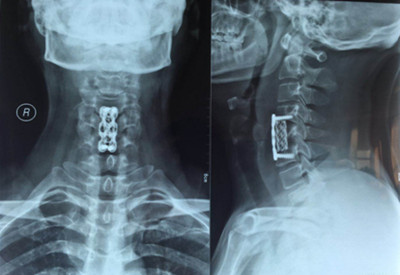

圖片二:

因患者年齡較輕,雙下肢無力癥狀明顯,病變區(qū)脊髓信號改變,保守治療病情會繼續(xù)發(fā)展,后期脊髓神經(jīng)變性,壓迫癥狀加重,嚴(yán)重影響肢體功能,必須盡早手術(shù)。骨一科主任楊志奎帶領(lǐng)曹熙、田濤、張凱迪醫(yī)師為其實施了頸椎前路頸5椎體次全切、椎管減壓植骨融合內(nèi)固定術(shù)。手術(shù)歷時3小時順利完成。術(shù)后第二天,患者雙手指麻木癥狀明顯緩解,四肢關(guān)節(jié)活動均正常。第三天配帶頸托保護(hù)下床活動鍛煉,雙下肢無力癥狀明顯減輕?;颊攥F(xiàn)已康復(fù)出院。

4月23日王先生來院復(fù)查:雙手指麻木感、雙下肢無力感消失,四肢肌肉力量恢復(fù),行走姿態(tài)正常,病情恢復(fù)理想。